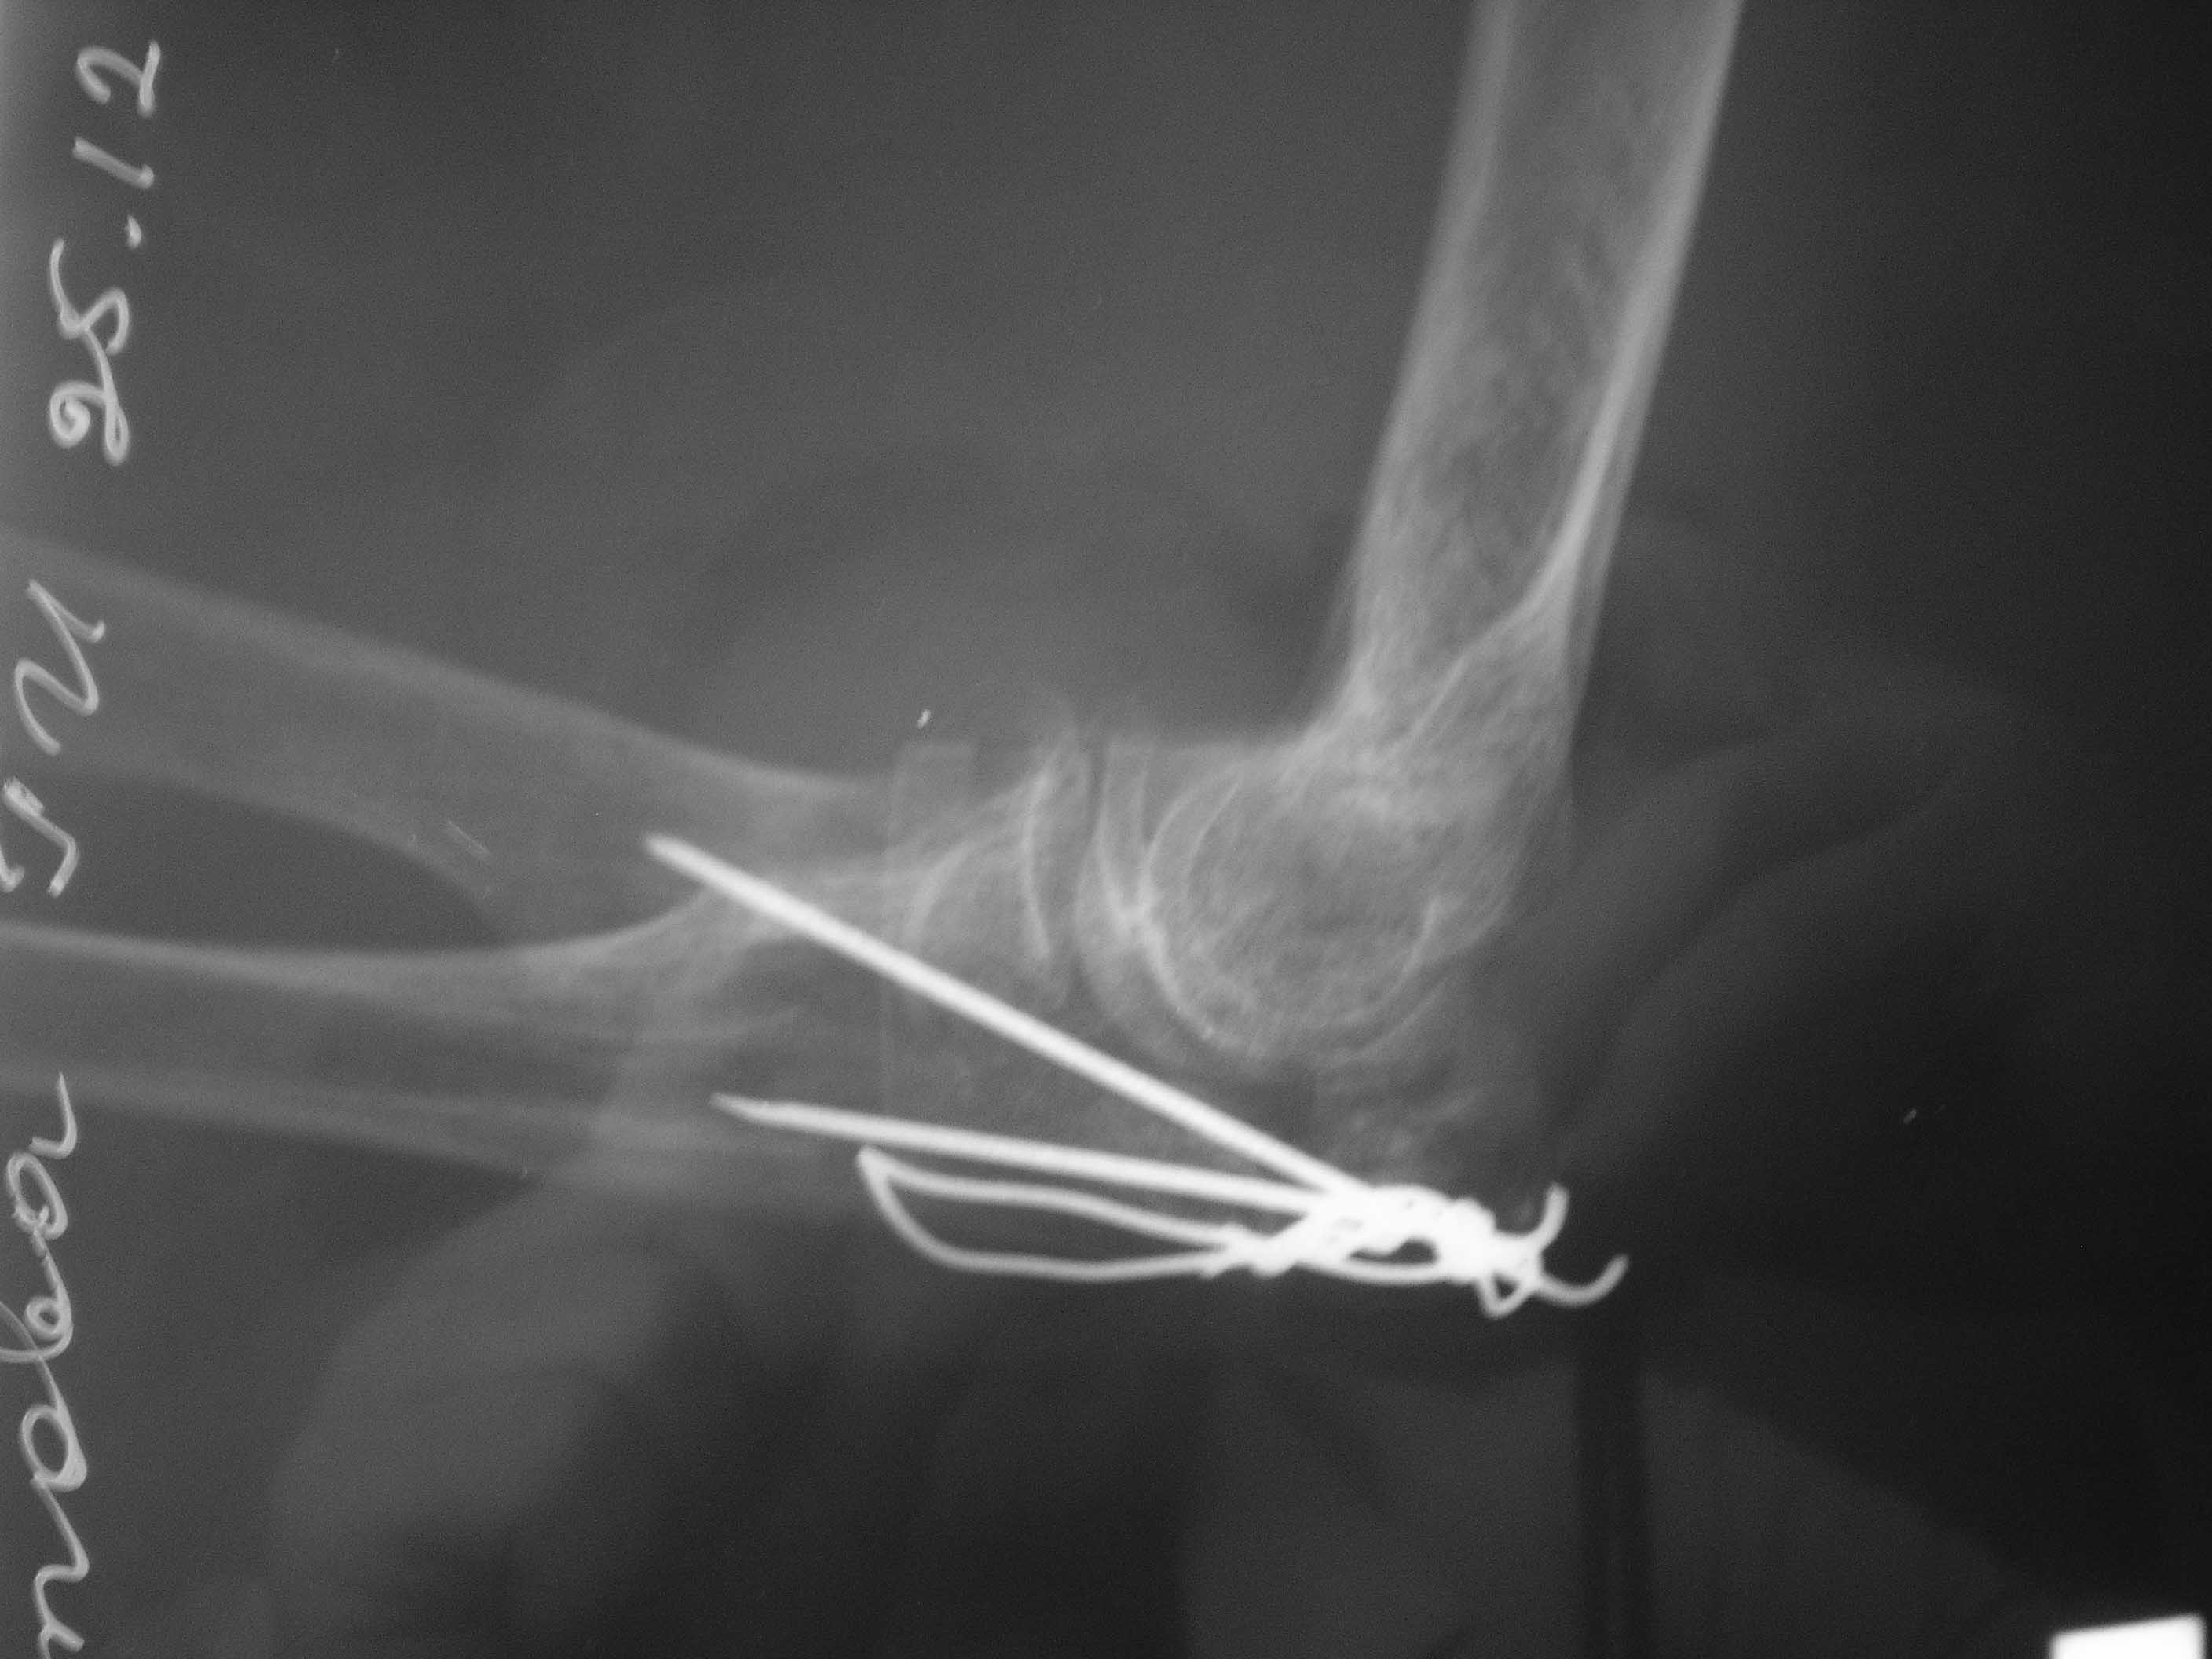

Первоначально на клиническом разборе планировалась костная аутопластика с фиксацией пластинкой или аппаратом внешней фиксации. Однако в течение нескольких дней у больной систематически отмечался подъем АД до 200-220 мм.рт.ст., трудно снимаемый гипотензивной терапией, назначенной по рекомендации терапевта. Через 1 неделю п/травмы больная взята в операционную и … снята со стола с очередным гипертоническим кризом (АД 230/100 мм.рт.ст.). Подключена терапия, на этот раз назначенная кардиологом. Повторное обсуждение случая с врачами отделения. Предложения: или от операции отказаться, или выполнить остеосинтез локтевого отростка, в любом случае - без наркоза. Учитывая «злокачественное» течение гипертонической болезни с исключительно лабильной гемодинамикой в ответ на малейшее эмоциональное волнение пациентки, решено выполнить остеосинтез спицами с проволочной петлей и костной аутотрансплантацией из дистального отломка локтевой кости (из этого же оперативного доступа) под проводниковой анестезией. АД удалось стабилизировать за 2 дня до операции. Через 2 недели после травмы больная вновь взята в операционную. Выполнена верхняя проводниковая анестезия по Соколовскому. Непосредственно перед началом операции на операционном столе у больной опять отмечен подъем АД до 190 мм.рт. ст. . В течение 30 минут анестезиологом проводилась коррекция АД и с давлением 150 мм.рт.ст. операция начата. После выполнения заднего доступа по Фарабефу обнажена зона перелома. Выявлен раздробленный перелом локтевого отростка с множеством промежуточных мелких костных фрагментов и отсутствием губчатой кости (остеопороз), проксимальный отломок представлен 3 –мя отломками размером 1-1,5см каждый, местами связанных между собой надкостницей. В момент ревизии костных отломков АД упало до 100/60 мм.рт. ст. Решено отказаться от выполнения костной аутопластики, и как можно быстрее заканчивать операцию. Произведен остеосинтез локтевого отростка двумя спицами и проволочной петлей, при этом обнаружено, что малейшее стягивание петли, проведенной в виде «обычной восьмерки» ведет к деформации локтевого отростка за счет компрессии (сминания) промежуточных фрагментов. В связи с этим спицы проведены перекрестно друг к другу, а проволока закручена вокруг выстоящих концов спиц (для увеличения стабильности проксимальных отломков), при этом закрученные концы ее не скушены, а уложены вдоль локтевого отростка для предупреждения вторичного смещения промежуточных фрагментов. Продолжительность операции – 35 минут. На контрольных рентгенограммах (доставленных в операционную уже после ушивания раны) – отломки в положении контакта, положение костных отломков локтевой кости удовлетворительное (см. фото 3,4). Гипсовая иммобилизация не проводилась. Правая верхняя конечность подвешена в косыночной повязке.

4) Вероятно, следует напомнить, что продольная (по оси локтевой кости) компрессия в случае раздробления костных отломков недопустима. Именно в связи с этим проведение двух спиц параллельно друг другу со стягивающей петлей является противопоказанием при многооскольчатых (и тем более раздробленных переломах). Проведение двух спиц не параллельно, а перекрестно друг к другу как раз и не дает компрессии в момент натяжения петли. В свою очередь, проволока в этом случае выполняет роль стабилизатора положения одновременно и спиц, и промежуточных костных отломков, предотвращая смещение их в стороны. Подтверждением этому являются этапные рентгенограммы (выполненные в конце декабря), на которых отмечено стабильное положение костных отломков и металлофиксаторов, несмотря на разработку движений в суставе.